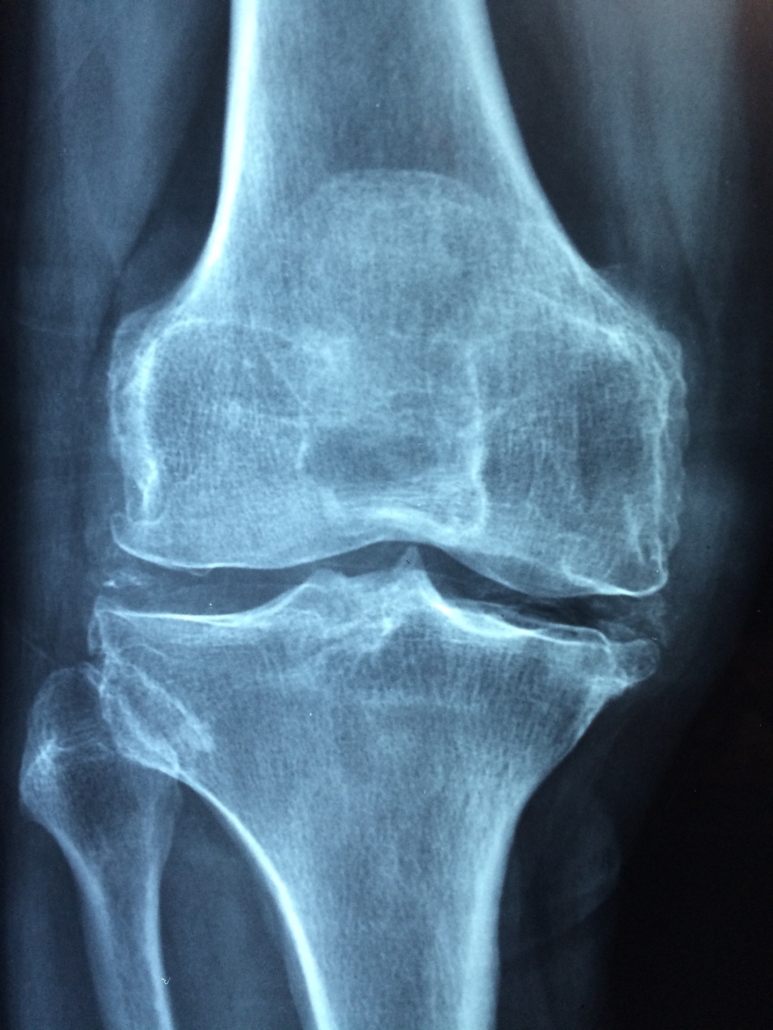

Rheuma im engeren Sinn wird heute als rheumatoide Arthritis bzw. primär chronische Polyarthritis (PCP) bezeichnet.